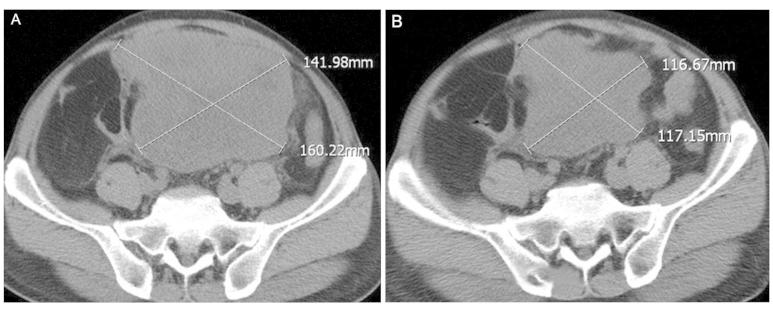

Multiple mesenteric well-differentiated (WD) liposarcoma is an extremely rare entity. The present study describes a case of multiple mesenteric WD liposarcoma, complicated by purulent inflammation, in a 59-year-old male who presented with abdominal pain and pyrexia of unknown origin. A computed tomography scan of the abdomen revealed a large, non-encapsulated mass in the abdomino-pelvic cavity, which was characterized by two components, a main portion of fatty density and a non-adipose solid portion. A re-evaluated CT scan, performed eight days later, revealed an enlargement of the non-adipose mass. A laparotomy was performed, and numerous separated fatty nodules and masses of various sizes were identified within the mesentery of the small intestine. The histological findings were consistent with an adipocytic subtype of multiple mesenteric WD liposarcoma, with the largest of the tumors complicated by purulent inflammation. The multiplicity of these tumors and the concurrent purulent inflammation in the present case make it unique.